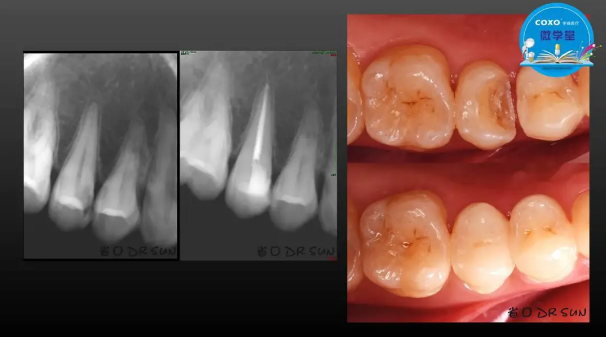

主講:孫書昱

主任醫(yī)師,牙體牙髓副主任, 廣東省口腔醫(yī)院牙體牙髓科 主任醫(yī)師。2003年碩士研究生畢業(yè),研究方向為牙體牙髓病學,擅長于牙體牙髓病的診斷、齲齒、牙髓炎、根尖周病的治療以及前牙美容修復。